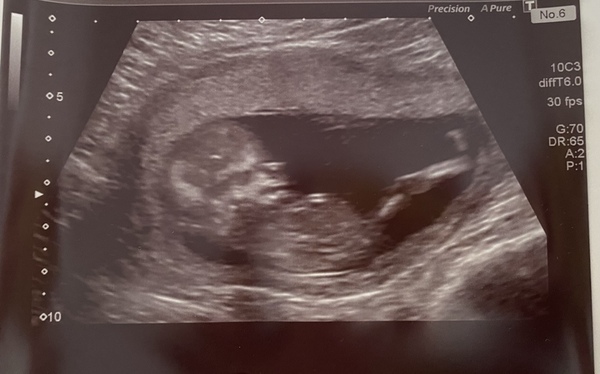

BessieBye · 02/11/2020 16:53

Hello @DontFadeAway!

This is our little baby at 12wks+3. Active, happy and apparently a little naughty 😂 look at that long leg!

Had to tell people not to start guessing girl or boy as we are wanting a surprise and I’ll be beside myself if people start guessing 😂

How are you? Xxx

@BessieBye oh what a lovely scan photo! Congratulations ♥️♥️ such a great shot of the leg, wow!!